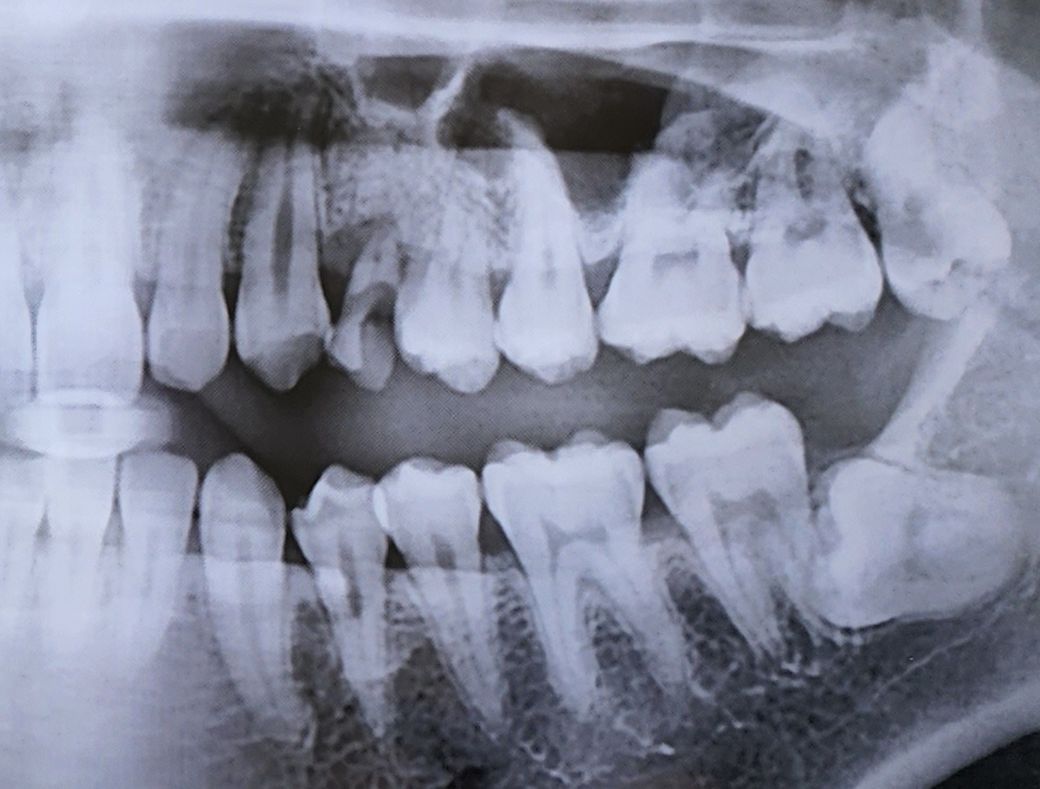

엑스레이 사진 상으로 충치 많아보이나요

상악 하악 6~7번 치아들 눈으로 보면 까만 점이나 까만 실선이나 이런게 보이긴 하는데 엑스레이 사진상으로 법랑질은 괜찮아보이기도 하고.. 또 어떤 의사분은 까맣게 보인다고 충치는 아니라고 하고.. 오우~~~ 누구 말이 맞는가요

일단 사랑니랑 24번 유치는 충치가 확실해서 빼려고 하고 있어요.

어금니 즉 제1대구치와 제2대구치의 교합면(씹는면)의 충치는 x ray 만으로 확인하기

어려우나 치아와 치아 사이 충치(인접면)는 현재 x ray 상에서도 확인됩니다.

충치에 대한 판단은 엑스레이와 직접 눈으로 보는 검사를 통해서 결정하게 됩니다.

사진상으로 치아사이 충치가 몇개가 있는것처럼 보이지만, 정확한것은 눈으로 보면서 최종 판단을 해볼 수 있습니다.

방사선 사진 상에서 까맣게 보인다고 해서 반드시 충치는 아닙니다. 말씀하신 파노라마 사진은 3차원 자료를 2차원으로 나타내기 때문에 방사선에 상당한 왜곡이 있을 수 있으며 방사선 x-ray 및 관구가 통과하는 각도에 따라서 충치가 아닌데도 tearing이 일어나서 검게 보일 수 있습니다.